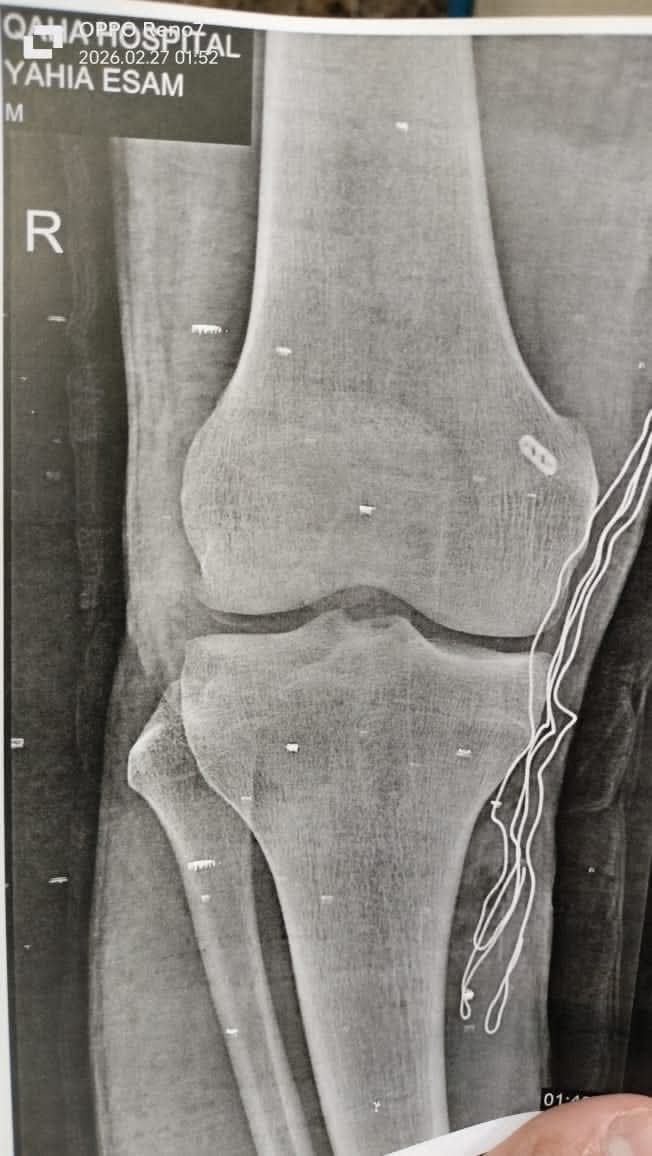

واستقبلت مستشفى قها التخصصي المريض وهو يشكو من آلام شديدة وعدم استقرار بمفصل الركبة، وعلى الفور تم إجراء الفحص الإكلينيكي اللازم، إلى جانب أشعة الرنين المغناطيسي، والتي كشفت عن وجود قطع بالرباط الصليبي الخلفي، وهي من الإصابات غير الشائعة مقارنة بإصابات الرباط الصليبي الأمامي المنتشرة بين الرياضيين.

وعقب التشخيص الدقيق، قرر الفريق الطبي التدخل الجراحي العاجل، حيث تم إجراء إعادة بناء الرباط الصليبي الخلفي بالمنظار باستخدام رقعة وترية، مع تثبيتها بواسطة زرار طبي ومسمار ذاتي الامتصاص، وفق أحدث المعايير الطبية المعتمدة في هذا النوع من الجراحات الدقيقة، وقد تكللت العملية بالنجاح واستقرت حالة المريض.